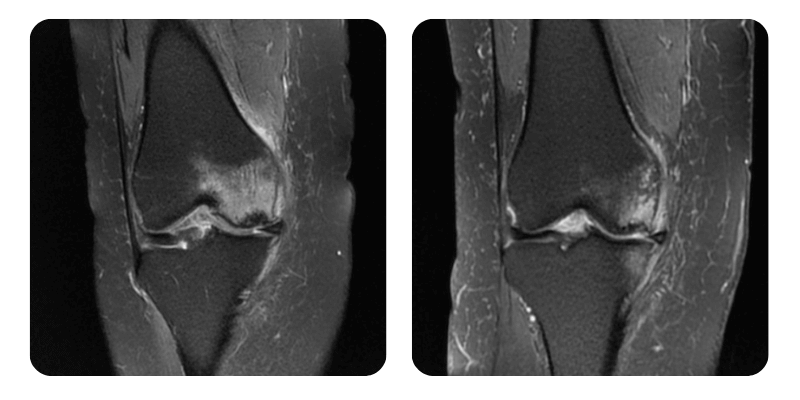

Prima

Dopo

S.I., 73 anni - Necrosi avascolare del condilo femorale destro

Diagnosi: Necrosi avascolare del condilo femorale destro.

Evoluzione: Mobilita nettamente aumentata, vascolarizzazione normale.

Prognosi: Riduzione dell'edema di circa l'80%.